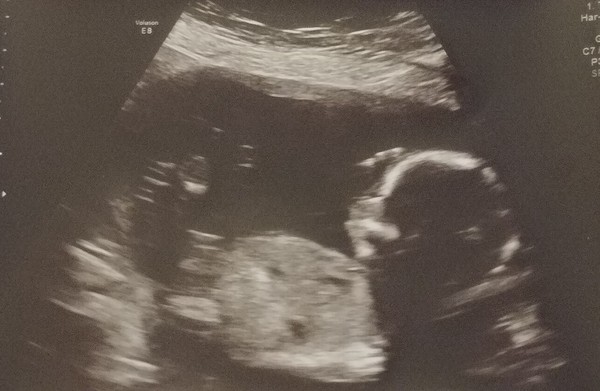

So had our scan yesterday but then came home and didn't feel too great, and now I'm having trouble staying asleep πŸ˜’

All seems okay though and it looks like we're having a boy 😍 So surprised, I was completely convinced otherwise. Also found out that my placenta actually is at the front so that explains a lot about not really feeling movements!

Congratulations @UnicornsandRainbows1 gorgeous picture of your SON! Glad all seems to be ol x

@UnicornsandRainbows1 gorgeous scan photo, congratulations on your boy! πŸ’™

@UnicornsandRainbows1 congratulations on a healthy scan and so exciting you know the sex. I am still undecided on whether we open that envelope. DH wants to open after our 20w scan if all is okay. I still don't know if I'd rather have a surprise.

Oh and major congrats @UnicornsandRainbows1! Lovely that you have found out the gender now. I am also convinced mine is a girl, so watch it will also be a boy! :)